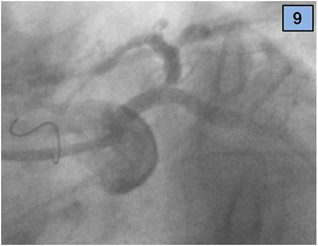

3. A guidewire was recrossed to LAD artery through the struts of the previously implanted stent (Figure 9).

Figure 9 A wire was recrossed to LAD artery through the struts of the LM and CX stent.